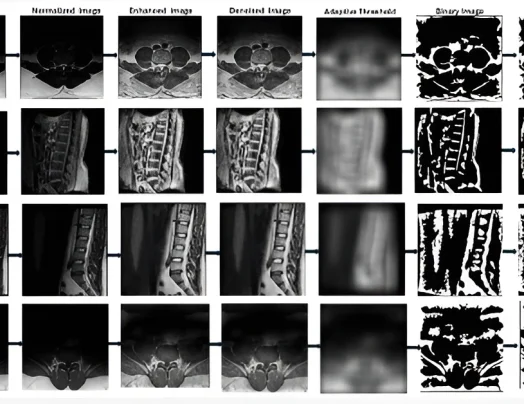

Developed a semi-automated framework for standardized vertebral measurement in lumbar spine MRI, improving reproducibility and reliability for spinal diagnostics and follow-up studies.